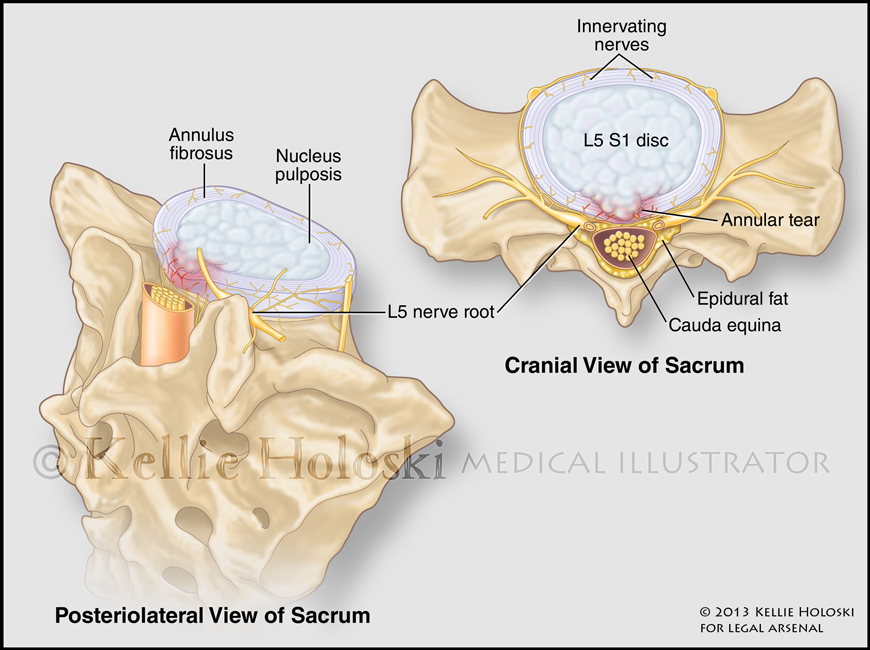

Sacrum with Herniated Disc,

Adobe Photoshop

Courtroom exhibit;

©Kellie Holoski -